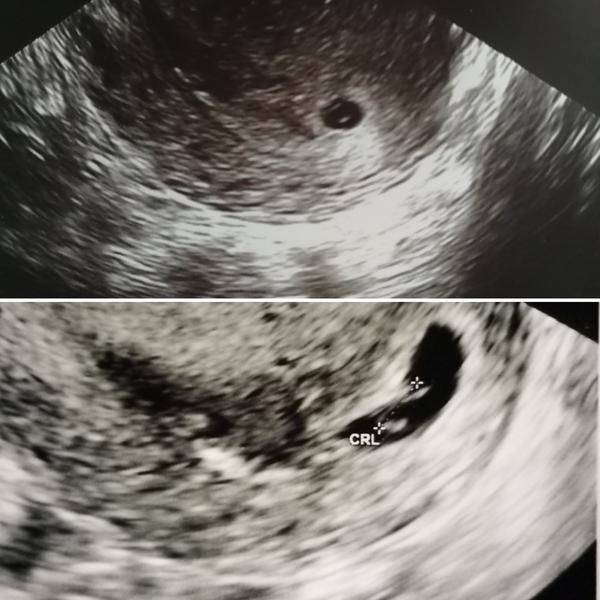

@gabina23 ahoj podla menstruacie sa neriadime lebo moja bola posledna 2.4. Takze by som mala mat +2tt ale ja som mavala pravidelne dlhe cykly 38d a ovulaciu som mala vzdy neskor a 12d lutealnu fazu, merala som si teplotu takze presne som vedela kedy bola ovulacia a 6tt+4 mi presne sedelo aj podľa toho ako mi to vypocitalo sono. U mna pokrok po 6 dnoch bol vidiet kukni na fotke.. O kyrete nepadla ani rec, doktorka povedala ze buduci tyzden uz bude srdiecko ale kontrolu mam az 20.6. Aby sme mohli uz aj knizku zalozit. V 6tt+4 nemusi byt vidiet srdiecko.